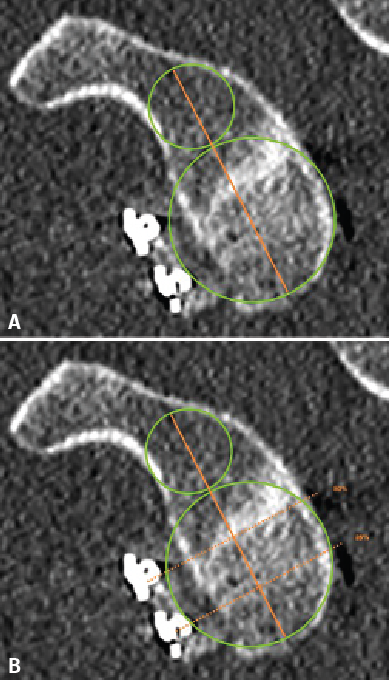

Figure 2. Evaluation of graft positioning in the sagittal section. Two lines are traced of a length equivalent to the size of the glenoid bone defect (B) and to the length of the graft covering the defect (A). Image A shows how most of the bone defect is covered by the graft - the latter therefore being considered to be well positioned. Image B shows that less than 90% of the bone defect is covered by the graft - the latter therefore being considered to be inadequately positioned.

Taking the posteroinferior glenoid border as reference, we traced a first circumference over its contour, and a second circumference above the previous one and tangential to the glenoid borders. The line joining the centre of both circumferences was taken to represent the axis of the glenoid cavity. Over this we estimated the point corresponding to the half and 25% of the glenoid height (Figure 1). The sagittal section was used to determine the position of the graft in the craniocaudal direction (Figure 2). The length (in mm) of the bone defect was measured (B), along with the amount of bone graft covering the defect (A). Percentage covering of the bone defect was estimated from the ratio between A and B. The graft was considered to be well positioned when the percentage coverage of the defect was at least 90%.